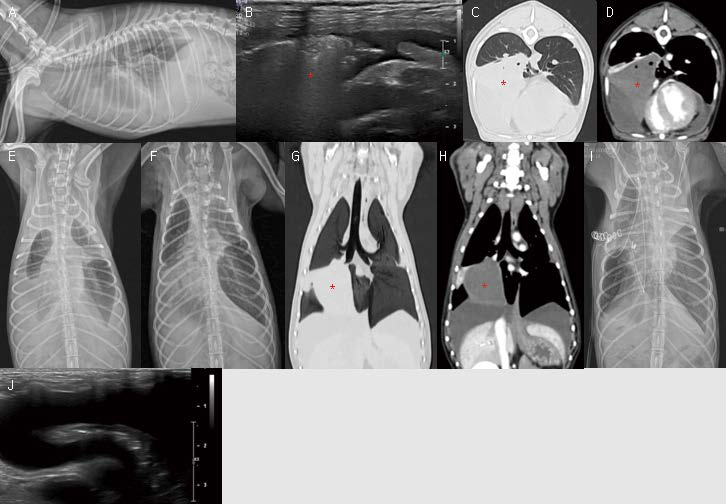

[대한수의사회지 24.png

12살 중성화 수컷 9.1kg 비숑이 한 달 정도 기침 증상으로 내원하였습니다. 흉부방사선 검사에서 우측 중엽 위치에서 연조직 밀도의 음영이 관찰됩니다(A, B). 폐초음파에서 우측 중엽은 정상 폐구조를 모두 소실되고 저에코의 outward bulging mass 양상으로 관찰됩니다. Tiny calcified spots을 포함하여 관찰됩니다(G, H). CT 검사에서 석회화를 동반한 이질적 밀도의 종괴가 우측 중엽에서 관찰됩니다(C, D, E, F). 초음파 가이드 FNA를 실시했을 때 Pulmonary carcinoma로 확인됩니다. Primary 폐 종양은 엑스레이에서 보통 lobar infiltration with mass effect 양상으로 관찰되며, 일반적으로 air bronchogram이 관찰되지 않습니다. 또한 석회화가 동반될 수 있습니다. 폐 초음파에서는 흉부방사선에서 관찰되는 소견 뿐만 아니라 clear cut margin 또는 finger shaped ramification이 관찰될 수 있고, 기관지 및 혈관 분포 이상을 관찰할 수 있습니다.

여기서 잠깐! 전이성 폐결절은 폐초음파 검사에서 어떻게 보일까요? 다음 환자는 호흡곤란으로 내원한 14살 중성화 암컷 Cocker spaniel 환자입니다. 흉부방사선 검사에서 폐야 전반에 걸쳐 reticulonodular interstital pattern이 관찰되는데, 전이? 염증? 명확하지 않습니다. 그런데 폐초음파를 보면 clear cut margin을 가지는 균질한 저에코의 둥근 결절이 보다 명확히 관찰됩니다. 이러한 양상은 대부부 폐전이 결절의 양상입니다. 폐 전이가 가능한 악성 종양을 가지고 있는 환자의 흉부 방사선 검사에서 뚜렷한 전이 소견이 관찰되지 않는다고 하더라도, 또는 lung periphery에 병변이 없어보인다고 하더라도, 폐초음파를 보면 lung periphery metastasis 결절이 생각보다 많이 관찰됩니다. 또한 lung periphery이므로, 초음파 가이드 FNA도 가능합니다.

<※증례 ⑥>

2살 중성화 수컷 Poodle이 호흡 곤란 증상으로 내원하였습니다. 일주일 전에 구토 설사 증상으로 대증 치료를 받았고, 이후 점점 기침이 늘고, 기력 저하, 식욕 저하, 호흡 곤란 증상이 악화되어 내원하였습니다. Plain X-ray(A, E)에서 양쪽 흉강에 다량의 흉수가 관찰됩니다. 다른 폐엽과 달리 오른쪽 중엽 또는 후엽의 밀도는 volume과 밀도가 증가되어 보이며, vesicular gas pattern이 관찰됩니다. 또한, 흉부초음파에서 다량의 흉수가 관찰됩니다. 다른 폐엽은 흉수로 인해 collapse되어 관찰되나, 오른쪽 중엽 또는 후엽은 크기가 오히려 커져 있으며, central portion으로 갈수록 hyperechoic gas bubbles로 채워져 관찰됩니다(B, *). 흉수 천자 이후 기본 흉부방사선 검사에서 보다 오른쪽 중엽으로 생각되는 폐엽의 종대 및 vesicular gas pattern이 잘 관찰됩니다(F). 흉수 천자 이후 환자는 일시적으로 호흡 상태가 개선되었습니다. 보호자님이 추가적인 검사 및 수술을 결정하지 못하셔서 3일 후에 CT 검사를 진행하게 되었습니다. CT 검사에서 오른쪽 중엽으로 가는 기관지가 급격히 단절(abrupt tapering)되어 있고, 오른쪽 중엽 자체가 크게 종대되어 관찰됩니다.

3일 전 흉부방사선 검사에서 관찰되는 다량의 vesicular gas pattern과 비교 시, 염전된 폐엽 내부로 gas bubbles이 매우 소량 관찰되는데, 염전 이후 시간이 지나 necrotic 변화를 보이는 것으로 생각됩니다(C, D, G, H). 수술 후 흉부방사선 복배상에서 왼쪽 전엽이 잘 관찰되지 않고, 흉수가 아직 많이 남아 있어(I), 흉부초음파 검사를 실시했을 때, 왼쪽 폐전엽 위치에서 흉수의 저류 및 collapse된 왼쪽 전엽이 관찰됩니다(J). Positional dependent lung collapse로 생각됩니다. 환자는 수술 후 특별한 complications 없이 임상 증상이 개선되어 퇴원하였습니다.

폐엽 염전(lung lobe torsion)의 진단은 CT 검사가 가장 유용합니다. 그런데 흉부초음파 역시 진단의 키가 될 수도 있습니다. Torsion된 폐엽은 보통 흉수에 둘러싸져 있습니다. 흉수로 인해 다른 폐엽은 일반적으로 collapse는 반면, torsion된 폐엽은 크기가 종대되어 있으며, 폐의 말초 부위는 hypoechoic하나(CT 검사에서 peripheral soft tissue attenuation으로 관찰), 좀 더 central portion은 multiple echogenic foci (gas)로 채워져 관찰(흉부방사선과 CT 검사에서 central vesicular gas pattern으로 관찰)되는 특징이 있습니다. 이 환자에서 흉부 초음파 B와 J 사진을 비교해 보면, 염전된 폐엽과 collapse된 폐엽을 보다 쉽게 구별할 수 있습니다. 다만, 흉수가 동반되지 않는 폐염전 환자도 있을 수 있으므로, 흉수가 없다고 폐염전을 배제시키기는 어렵습니다. 또한 폐염전 발생 시간에 따라 폐엽의 vesicular gas pattern 정도, necrosis 정도, 폐엽의 종대 정도가 달라질 수 있으므로 유의해야 합니다.